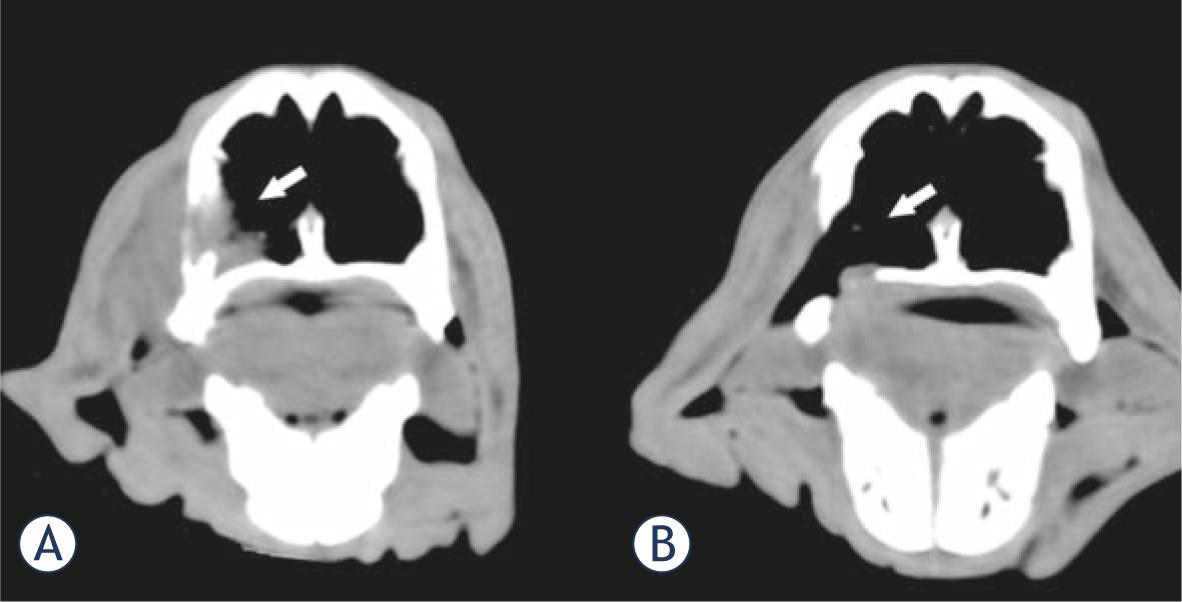

The patients remained in follow-up for 32 months, with no relapses in the treated area. This means that 91% objective responses (OR) were obtained. Figure 3, pictures the CT scan of patient 11 showing a complete response obtained with the treatment.

CT image of patient 11 before and after the treatment. (A) The tumor can be seen occupying the lateral inferior part of the left nasal passage (white arrow). (B) Two months after a single treatment a CR was obtained; as readily observed, the tumor tissue is absent leaving a defect in the nasal wall (white arrow).